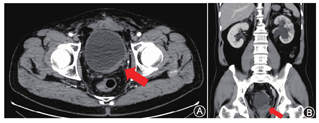

患者,男,56岁。因膀胱镜检查发现膀胱肿瘤复发1个月于2021年11月29日收入北京大学第三医院。患者2012年诊断为左侧输尿管口旁膀胱癌,其后有开放膀胱部分切除术史、同步放化疗治疗史、4次经尿道膀胱肿瘤切除术史。既往有高血压病、甲状腺功能亢进病史,药物控制良好;无严重心脑血管合并症。患者本次入院前无血尿,无尿路刺激症状,无腰痛。体质指数24.7 kg/m2,美国东部肿瘤协作组评分0分。术前前列腺特异性抗原(prostate specific antigen,PSA)为2.35 ng/ml。直肠指检:前列腺质韧,大小正常,未及结节,肛门括约肌收缩力弱。泌尿系增强CTU检查:膀胱左后壁肿物,不除外T3期膀胱癌,左肾积水较前进展,淋巴结未见明显肿大(图1)。